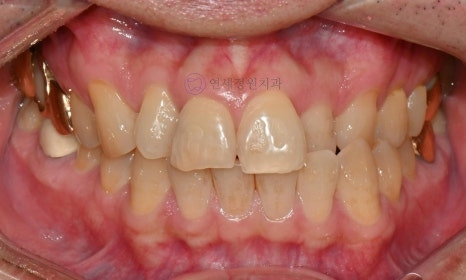

Before Shade: A3.5 / After Shade: A2